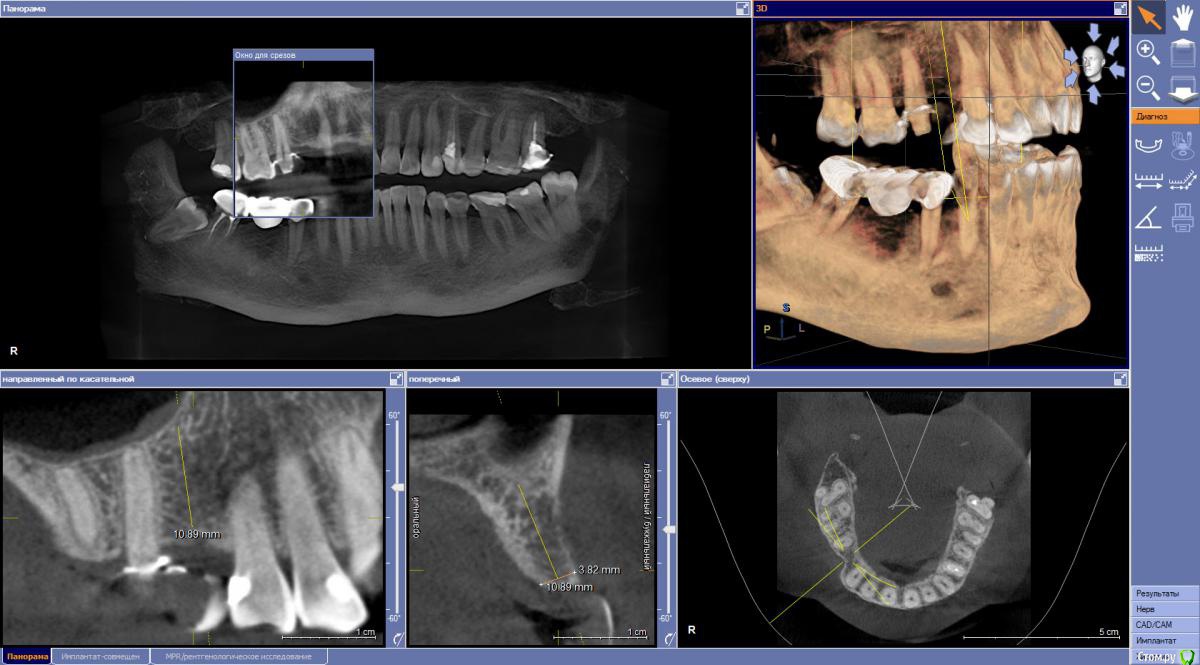

Estes Опубликовано 13 июля, 2018 Поделиться Опубликовано 13 июля, 2018 Здравствуйте. Имеется система MIS C1 и ситуация на КТ.Предложены варианты плана лечения:Курс пародонтолога и далееа) Имплантация 3.3*10 мм + Biooss+Biogide и возможно закрытый синус, затем - протезирование одиночками 15 и 14 на импланте или б) эндо 15+ВКВ+ м/к мост. протез 15-13 В варианте а) лично меня смущает диаметр самого импланта - думаю, что тонковат.А пациентке неочевидны плюсы применения импланта при затраченных усилиях. Подскажите-помогите определится, или свой вариант в этой ситуации? Ссылка на комментарий

колесников Опубликовано 14 июля, 2018 Поделиться Опубликовано 14 июля, 2018 15 оставить. 14 : не знаю как с с1,у астры например 3.0 -11мм и Насколько я помню мис и тд,шейка шире чем заявленный диаметр. Собственно любой Имплант в этой области будет вестибулярно без кортикалки в последствии,так что сильно не переживайте,а действуйте сообразно этому знанию. Считаю биос тут не нужен и даже вреден и отслаивать не нужно. Я бы так сделал: раскрыл и подшил роллом,поставил имплант 3.3-3.5 на 9-10. Заглубил на 2-3 мм. Апекс может войти в пазуху на 1-2 мм-не критично.Позиция с расчетом на винтовую. Сст с бугра вестибулярно полоской вертикально. Слепки и немедленная нагрузка. Ссылка на комментарий